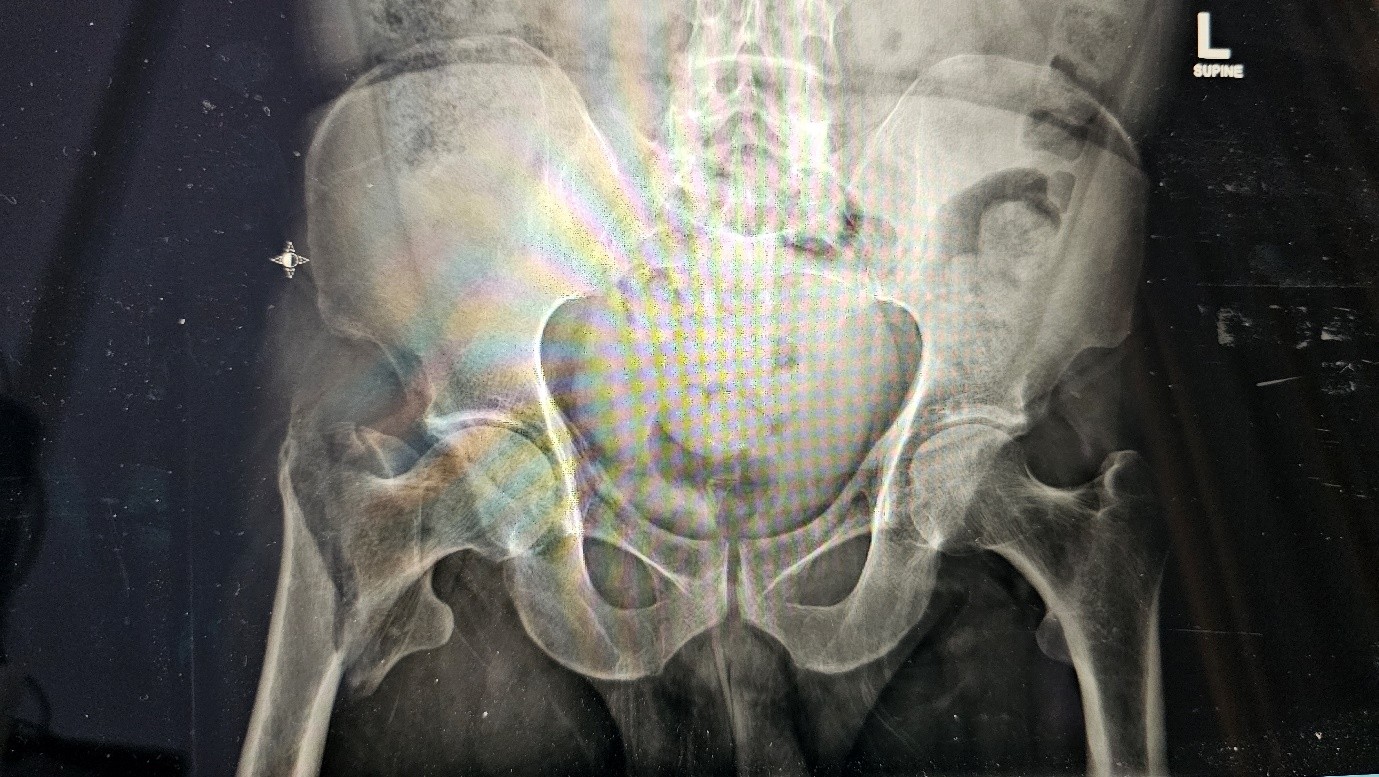

The patient, a 75-year-old female, presented to the emergency department following a fall at home. Radiographic evaluation revealed a comminuted intertrochanteric femur fracture on the right side. The patient was admitted for surgical management after appropriate medical and anesthetic clearance.

Post fall xray :

Fig 1

Fig 2

Figure 1

Figure 2